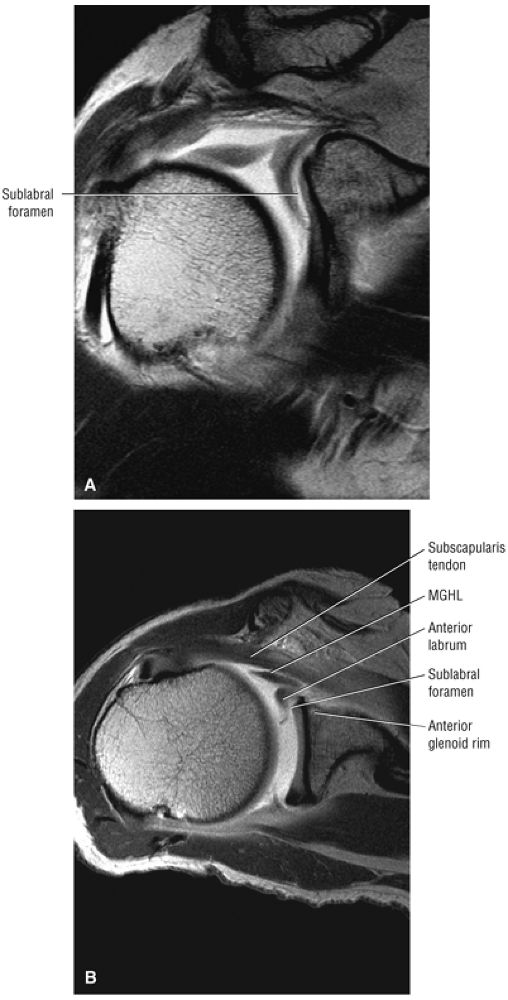

A separate FS PD-weighted FSE sequence is used to increase sensitivity to fluid and to identify paralabral cysts, articular cartilage labral avulsions, and muscle edema (Fig. 8.4). FSE sequences are less sensitive to intralabral signal intensity in the spectrum of degenerations or tears unless there is imbibed fluid. FSE (FS PD FSE) images, however, are superior for the demonstration of labral morphology in cases of avulsions or contour abnormalities.

without a FS PD FSE sequence to improve sensitivity for fluid and subtle labral tearing at the glenoid rim attachment.

FIGURE 8.4 ● (A) Axial FS PD FSE image shows intact and congruous humeral head and glenoid articular cartilage surfaces (arrows), separate from the high-signal-intensity intra-articular contrast. (B) PD FSE contrast without FS is shown in an axial image of a Bankart lesion. Chondral surfaces are not as well demonstrated. (C) Excellent contrast is shown between the avulsed anterior labrum and the anterior glenoid rim on the corresponding sagittal FS PD FSE image.